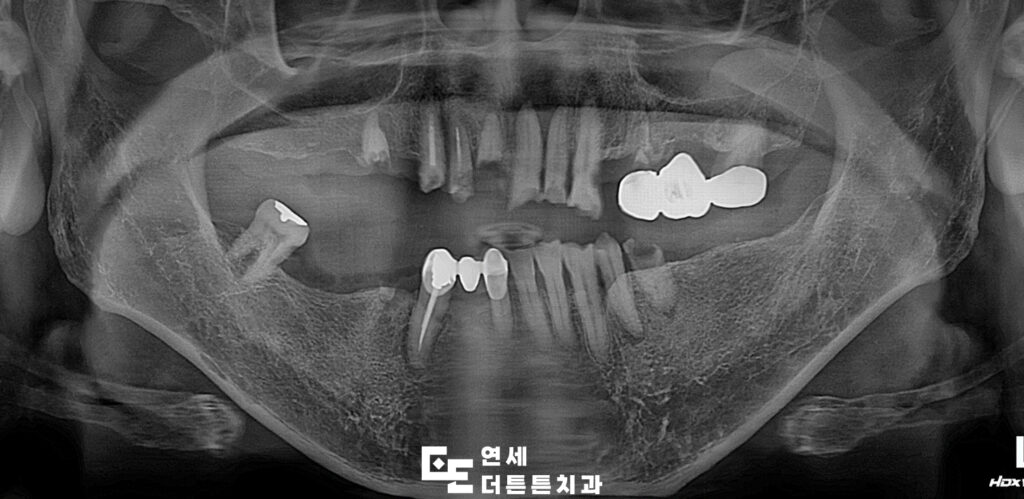

환자분께서는 구강 내 어금니 부위를 거의 상실하신 채로, 남아 있는 치아들도 부러져 제 기능을 하지 못해 치료 상담을 위해 방학역치과에 내원해 주셨습니다.

다수의 치아가 손상되거나 상실된 상태로 내원하였으며, 잔존 치아 또한 심한 우식과 변색, 구조적 약화가 동반된 상태였으므로 일부 치아는 보존이 어려운 상태였기 때문에 발치를 진행하였고, 남아 있는 치아 중 사용 가능한 치아는 신경치료 및 보강을 통해 최대한 활용하는 방향으로 치료를 계획하였습니다.

먼저 예후가 좋지 않은 치아들을 발치하고 결손 부위에는 임플란트를 식립하여 기능적인 지지 기반을 형성하였으며 최종 보철물이 들어가기 전 기간동안 사용하실 수 있는 임시틀니를 제작해 드렸습니다. 임플란트가 뼈에 제대로 붙기까지는 시간이 필요하며, 일반적으로 상악은 약 6개월, 하악은 약 4개월이 소요되어 그 기간동안 사용하시며, 최종 보철물에 대한 전반적인 상담도 충분히 진행할 수 있도록 하였습니다.